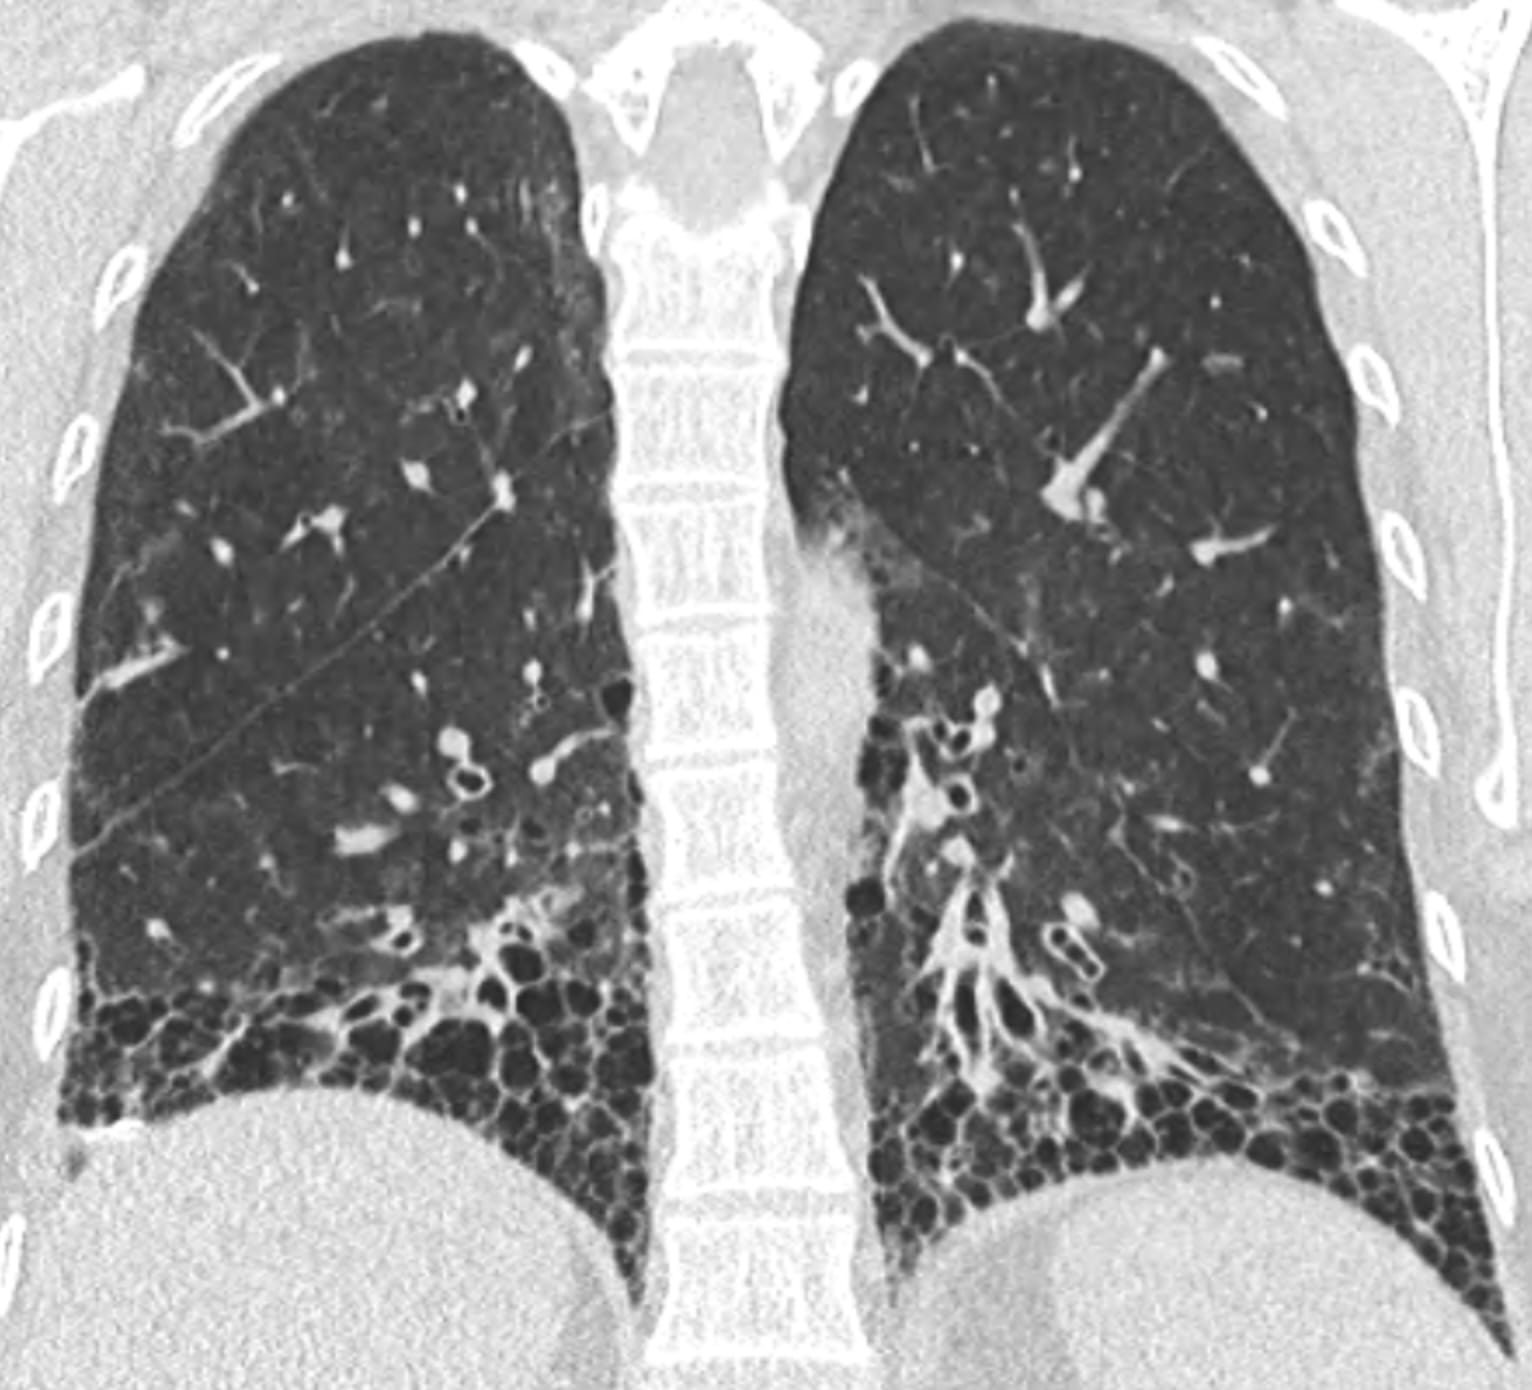

- Usual Interstitial Pneumonia